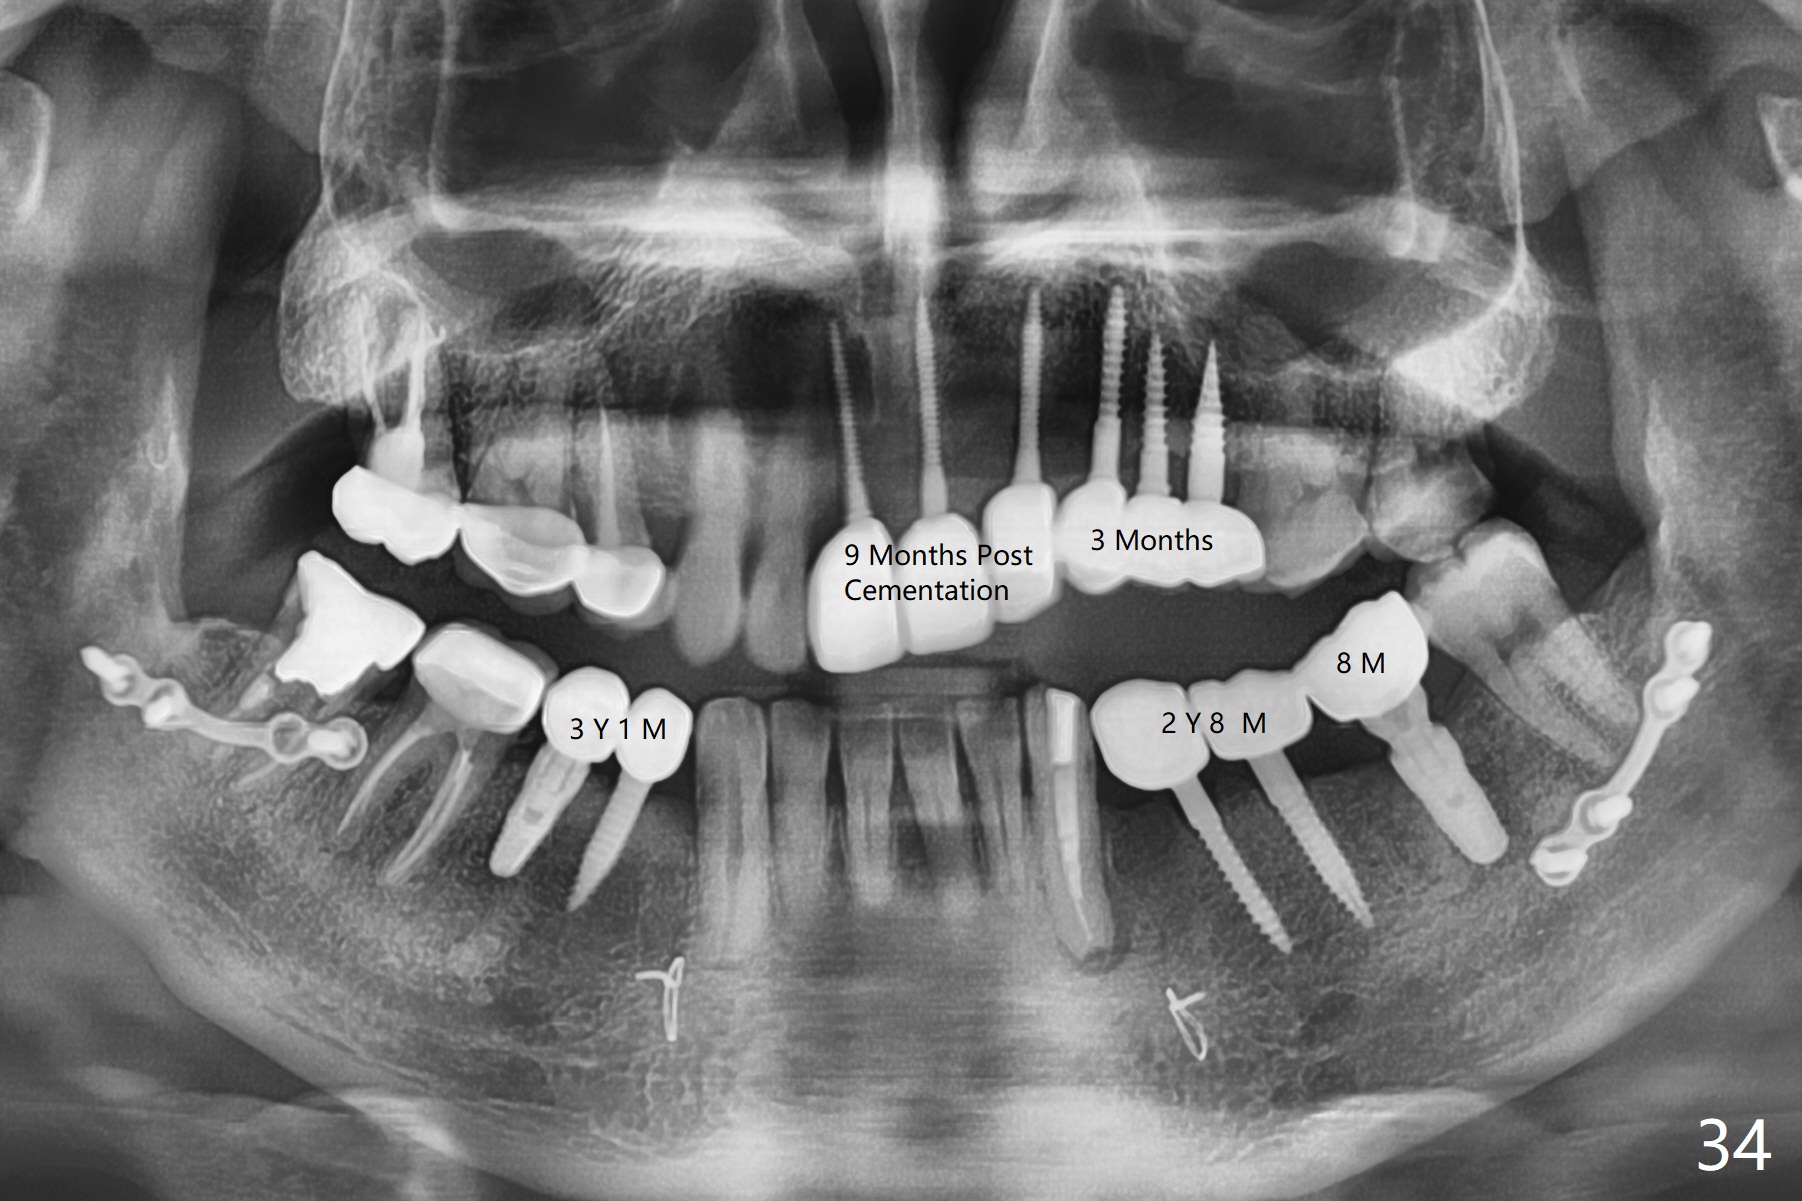

Three months later, he returns for follow-up; the soft (Fig.32,33) and hard (Fig.4) tissues remain healthy. The sizes of the implants are shown below.

| # | 8 | 9 | 10 | 11 | 12 | 13 | 19 | 20 | 21 | 28 | 29 |

| mm | 2x14(2) | 2x14(4) | 2x14(2) | 2.5x12(4) | 2.5x10(2) | 3x10(2) | 5.3x12 | 3x14(4) | 2.5x14(4) | 3x14(2) | 4.5x12 |